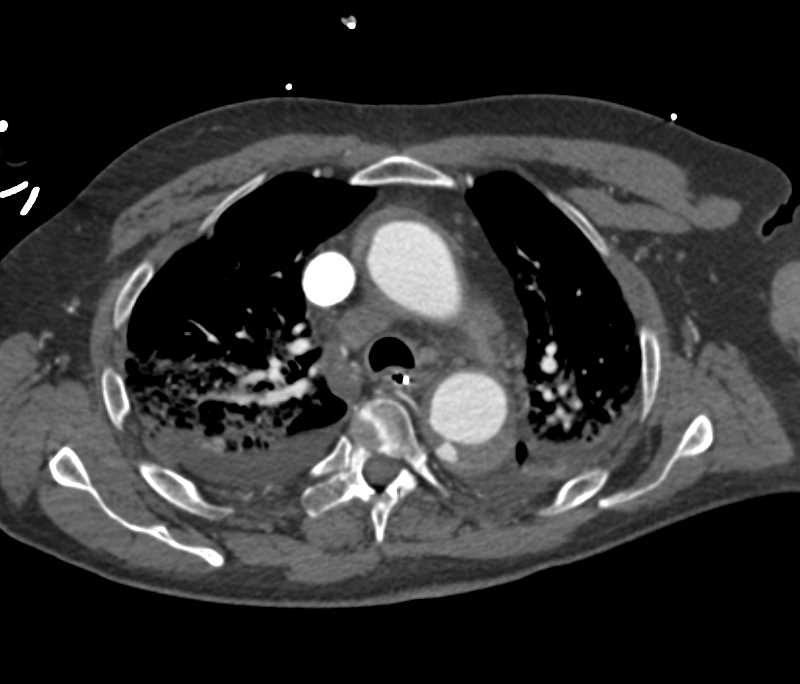

Intramural Hematoma with Ulceration